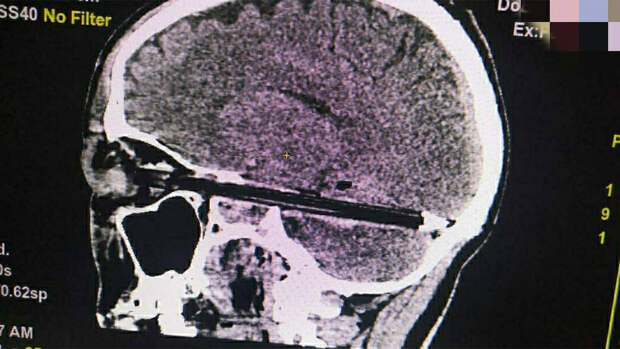

При этом пострадавший рассказывал, что повреждения нанес себе самостоятельно во время нервного срыва.Ранее сообщалось, что в Ростове-на-Дону был экстренно госпитализирован мужчина с шариковой ручкой в мозгу. Ручка повредила ему глаз и вошла в мозг на весь диаметр полости черепа, при этом она прошла в миллиметре от важнейших сосудов и ствола головного мозга. Врачи прооперировали пострадавшего, после чего он был переведен в реанимацию.